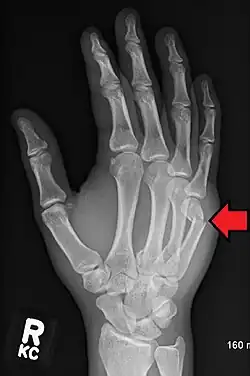

A healed fracture of the neck of the 5th metacarpal

Prognosis for these fractures is generally good, with total healing time not exceeding 12 weeks. The first two weeks will show significantly reduced overall swelling, with improvement in clenching ability showing up first. Ability to extend the fingers in all directions appears to improve more slowly. Hard casts are rarely required, and soft casts or splints can be removed for brief periods of time to allow for cleaning and drying the skin underneath the splint.[11] Pain from injury varies person to person as with most injuries. Depending on the individual a course of over the counter or narcotic pain medication will suffice. Muscle atrophy of 5 to 15 percent may be expected, with a rehabilitation period of approximately 4 months given adequate therapy. In the mildest of cases, full rehabilitation status can be achieved within 3 to 4 months.